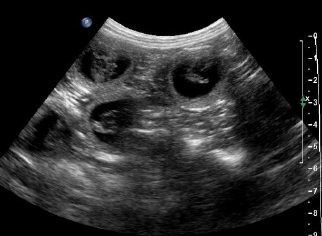

ULTRASSONOGRAFIA

(Cai na prova)

Da para ver o feto pequenino, e uma linha fina se tiver é a membrana amniótica que é quem recobre cada feto individualmente

Muito usada para ver funcionalidade, analisar órgãos, é em tempo real.

Aqui o liquido é enegrecido.